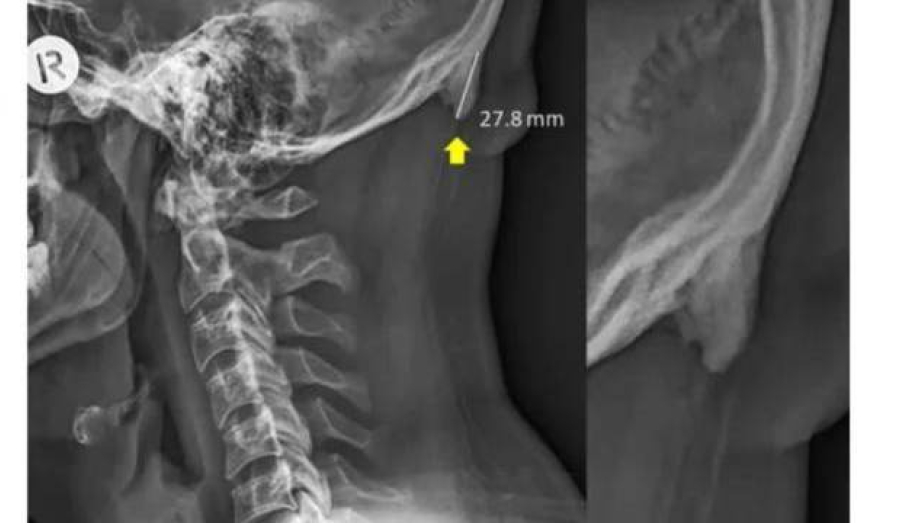

Австралийские ученые установили, что смартфоны провоцируют рост определенных костей черепа - роговидных шипов, представляющих собой костные наросты на задней части черепа. Они начинают образовываться из-за слишком частых наклонов головы.

Пользователи смартфонов чаще всего непроизвольно наклоняют голову вперед, поближе к экрану. Вес тела переносится с позвоночника на мышцы задней части головы, в сухожилиях и связках начинает расти роговидный шип.

В норме его длина не должна превышать трех миллиметров. Ученые изучили рентгеновские снимки 1200 добровольцев и пришли к выводу, что почти у 41% людей в возрасте до 30 лет размер шипа составляет от десяти до 31 миллиметра. Чаще всего "рога" встречались у мужчин.

Раньше такие наросты находили у пожилых людей, которые большую часть жизни занимались тяжелой физической работой. Пациенты испытывали хронические головные боли и неприятные ощущения в шее. Роговидные шипы у добровольцев не доставляли им дискомфорта. Их возникновение ученые связали с возросшей нагрузкой на мышцы шейно-черепного отдела из-за использования смартфонов, а не с генетической болезнью или последствиями перенесенных травм.